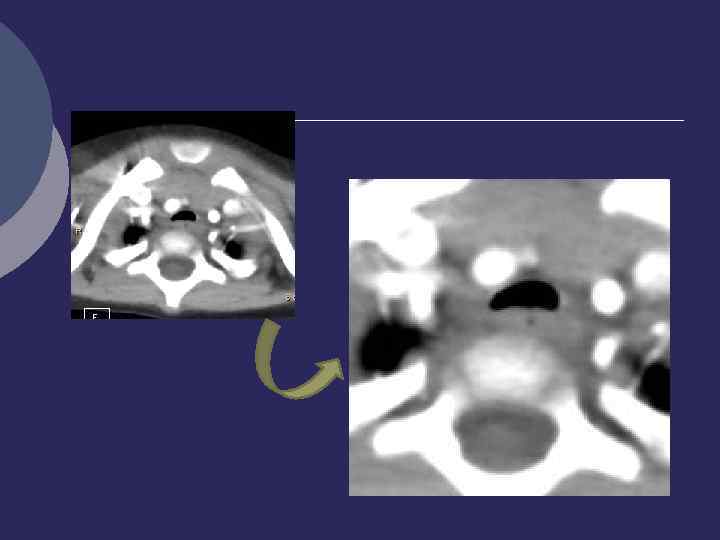

КТ. Трахеальный бронх Транспозиция верхнедолевого бронха в трахею Признаки ХНЗЛ трахеальной доли

Сепарация в/долевого бронха с транспозицией Б 1 в трахею В 2, 3

Сепарация правого в/долевого бронха с транспозицией Б 1 в трахею. МРТ.